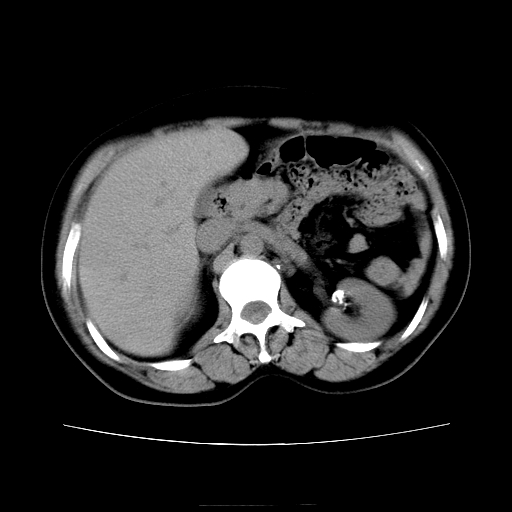

女45y多次(7次)碎石,结果不理想!曾碎石后尿出小碎石,仍腰痛,要求ct,其它不详.本人更倾向于钙化斑!无肾实质破坏,积水等提示集合系统无梗阻.另外腹腔多处钙化.是否结核后改变!谢谢赐教!

1)双肾结石。2)脾脏钙化灶。3)腹膜后多发淋巴结钙化。

尿路结石与腹部淋巴结钙化共存,建议v尿路造影检查,免得钙化灶冤枉为结石受罚。

考虑双肾结石,肾脏实质无破坏表现,没有结核病史,不考虑肾结核,